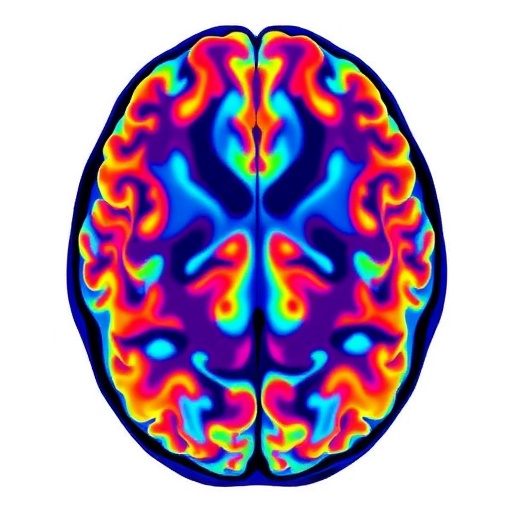

Neuroimaging Reveals Microstructural Brain Changes in Parkinson’s

In a groundbreaking study set to reshape our understanding of Parkinson’s disease (PD), researchers have presented compelling neuroimaging evidence that highlights intricate microstructural changes in the brains of patients experiencing subjective cognitive decline. This new research, published in the prestigious journal npj Parkinson’s Disease, offers unparalleled insights into how Parkinson’s disease affects the brain at a cellular and microstructural level long before overt cognitive symptoms become clinically apparent. Such findings hold the promise of aiding early diagnosis and potentially guiding therapeutic interventions tailored to halt or mitigate cognitive deterioration in affected individuals.

The study harnesses advanced neuroimaging techniques, leveraging cutting-edge diffusion tensor imaging (DTI) methods that allow unprecedented visualization of brain microstructure. These imaging modalities measure the diffusion of water molecules in brain tissue, providing indirect yet highly sensitive markers of axonal integrity, myelin density, and microstructural complexity. By applying these tools, researchers have demonstrated subtle yet statistically significant alterations in white matter tracts connecting critical cognitive hubs in Parkinson’s patients with subjective cognitive complaints.

One remarkable aspect of the findings is the identification of microstructural deteriorations in the frontostriatal circuits, which are crucial for executive functions, attention, and working memory. The frontostriatal pathway is a neural network well-known for its role in motor control but equally indispensable for cognitive processing. Decline within these tracts may explain the early cognitive symptoms experienced by patients even before measurable deficits surface in standard cognitive assessments.

Additional disruptions were noted in the limbic system, especially within white matter pathways linked to the hippocampus and amygdala. These regions are traditionally associated with memory consolidation and emotional regulation. The imaging evidence suggests that the neurodegenerative footprint of Parkinson’s disease extends beyond classic motor circuits, potentially involving networks fundamental to mood and memory processing long before overt dementia develops.

Among the most compelling technical achievements in this work was the integration of multi-shell diffusion imaging with advanced modeling algorithms. These methods allowed researchers to disaggregate various tissue compartments and characterize microstructural features such as neurite orientation dispersion and density. This granularity surpasses older DTI techniques that offer only aggregate measures like fractional anisotropy, enabling a more nuanced understanding of brain tissue pathology at the microscopic level.